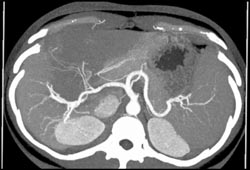

Diagnosis

Hemangioma